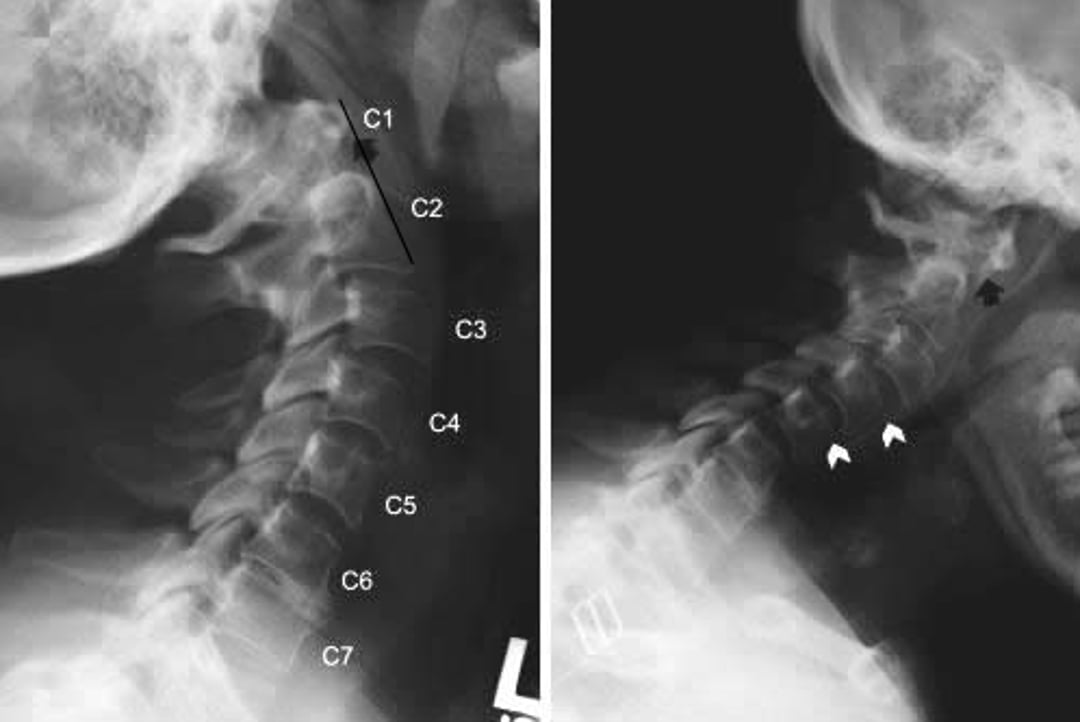

Phim chụp X-quang cột sống cổ cho thấy tình trạng bán trật khớp đội trục và bán trật khớp dưới trục ở bệnh nhân bị viêm khớp dạng thấp. Các hình ảnh nhìn từ mặt bên của cột sống cổ được chụp ở phần mở rộng cổ (bên trái) và uốn cong (bên phải). Trong chỗ uốn cong, vòm trước của C1 rất xa so với thân của C2 (phía sau mũi tên đen), biểu thị sự mất vững trước. Điều tìm thấy này không rõ ràng trong phần mở rộng (mũi tên màu đen), chứng minh rằng mất vững khớp đội trục thì không cố định. Trượt về phía trước (thân đốt sống trên trượt về phía trước, được thể hiện bằng mũi tên màu trắng) cũng xuất hiện ở C2-C3 và C3-C4 khi duỗi và ở C3-C4 và C4-C5 khi gập.